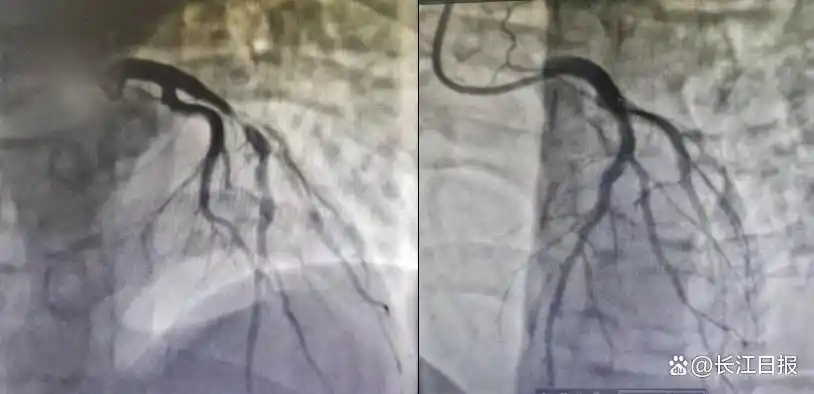

• 小伙熬夜+酗酒引發(fā)心梗,不良生活習(xí)慣正在摧毀年輕人的心臟

小伙熬夜+酗酒引發(fā)心梗,不良生活習(xí)慣正在摧毀年輕人的心臟

“以為年輕扛得住,沒(méi)想到死神離得這么近。”在武漢科技大學(xué)附屬天佑醫(yī)院CCU(心臟重癥監(jiān)護(hù)室)病房里,劫后余生的22歲青年彭某(化姓)仍心有余悸。一場(chǎng)因長(zhǎng)期熬夜